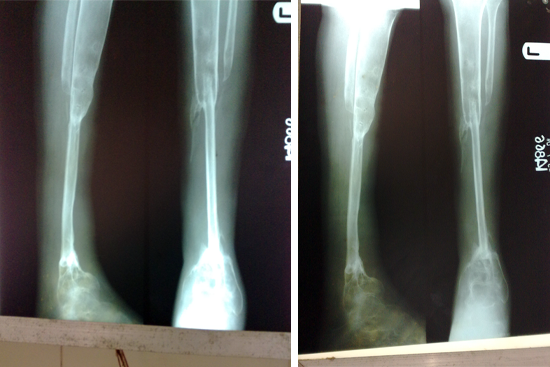

Tibialisation Of Fibula

Shankar Giri

Sudama

Wagh